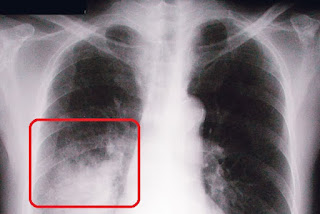

gambar xray jangkitan paru-paru